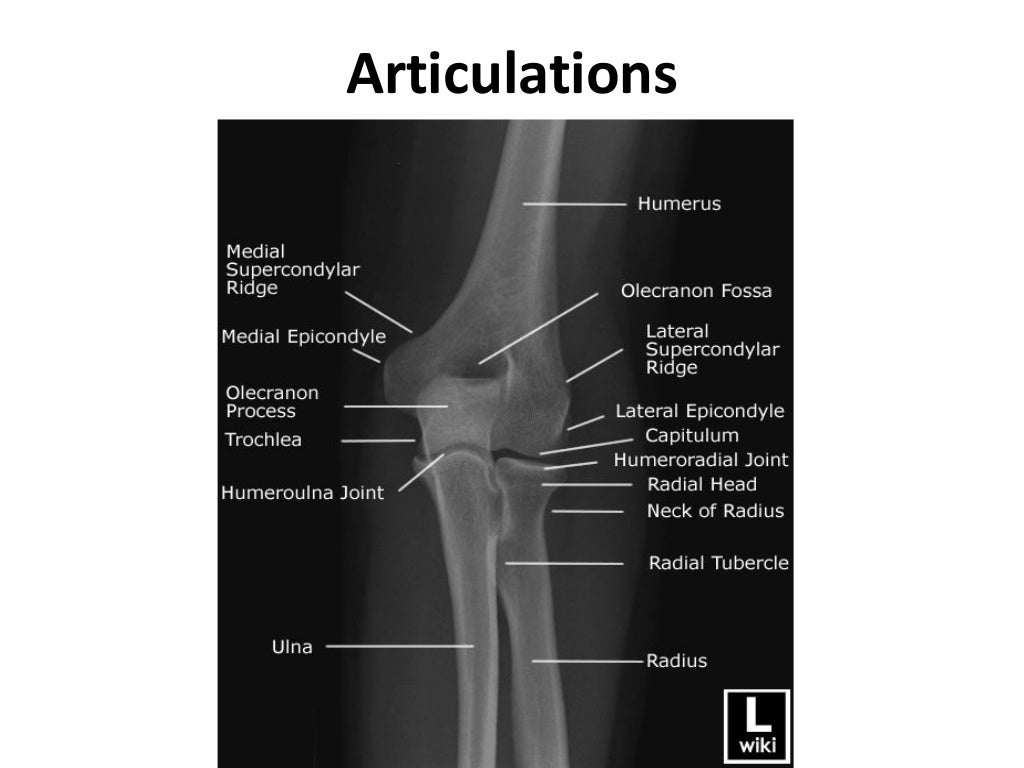

Labeled Xray Of Elbow . The elbow series is a set of radiographs taken to investigate elbow joint pathology, often in the context of trauma. Radiographs of the elbow and wrist can exclude malalignment of the elbow joint and distal. Check the anterior humeral line: In young athletes, osteochondritis dissecans (ocd) and apophysitis should be considered. Check each bone in turn: Drawn down the anterior surface of the. Pay particular attention to structures that are superimposed i.e. It usually comprises an ap and lateral projection, although. The traumatized elbow is discussed above. On “anatomical parts” you can choose between two types of labels: Normal oblique radiograph of the elbow with labeling of relevant anatomy.